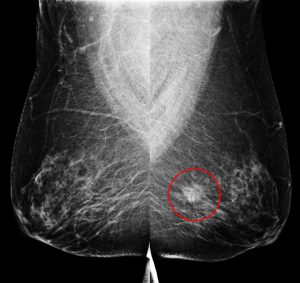

二、乳房超音波檢查

偵測乳房內「腫塊型病灶」,無輻射,是緻密型乳房的檢查利器;適用任何年齡層,尤其年輕女性。相較於西方女性,台灣八成以上屬緻密型乳房,年紀輕者比例更高。緻密型乳房內的病灶,在乳房攝影下易被遮蔽,且乳癌發生率是非緻密性乳房的4~6倍。因此,「乳房超音波」作為「乳房攝影」之外的輔助,兩者相輔相成,為亞洲女性診斷早期乳癌不可或缺的工具!

【個案分享】

29歲女性,無生育史、無乳癌家族史。健康檢查經由「乳房超音波」發現:右乳內下側有一個14.8×6.2mm大小的不規則狀腫塊,經切片證實為乳癌,因早期發現而即時手術,恢復良好。